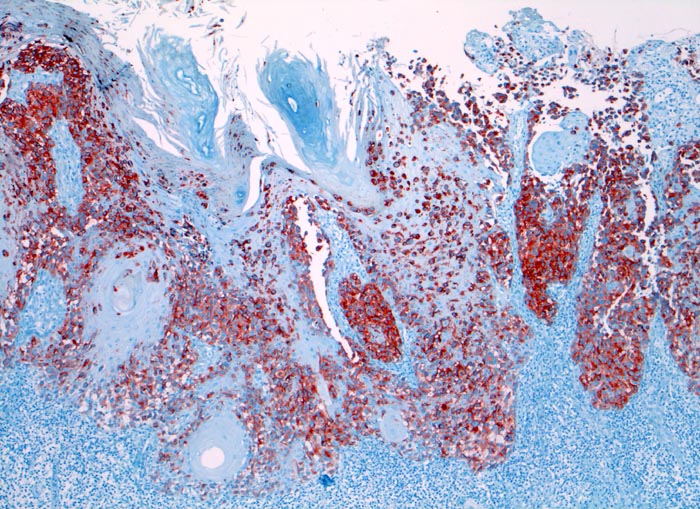

l/ HMB-45

HMB-45

Anfärbung:

Zytoplasma

Reaktion im Normalgewebe:

Aktivierte Melanozyten und Naevi, Mammaepithel und Schweissdrüsenepithel.

Reaktion in Neoplasien:

HMB-45 wird in diversen melanozytären und nicht melanozytären Tumoren exprimiert:

Naevi (meist nur oberflächlich)

Malignes Melanom (90% Primärtumoren, 80% Rezidive und Metastasen, desmoplastische Variante meist negativ)

Angiomyolipom

Lymphangioleiomyomatose

Klarzelltumor der Lunge (Sugar tumor)

Einzelne Mammakarzinome, Speicheldrüsentumoren, Karzinome, multiple Myelome

Diagnostischer Nutzen:

Identifikation der verschiedenen HMB-45 positiven Tumoren.

Spezifität für maligne Melanome höher als S-100, aber niedrigere Sensitivität.